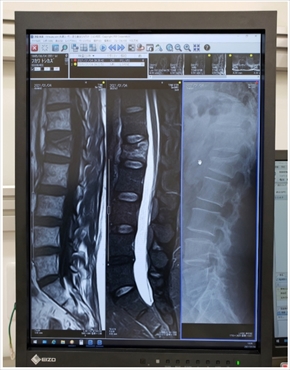

4日にようやく病院を受診した布川さんは、MRIとエックス線検査の結果を報告。腰は第1腰痛の圧迫骨折で全治2カ月、右肘は関節内骨折で全治6週間だったそうで、「打撲どころか、 折れてんじゃん……そりゃ、痛いはずだよなぁ…!」と本人としても納得だったもよう。1人暮らしため入院を勧められたそうですが、「なんとか頑張ります! っと帰って来ました〜」と現在は自宅療養を続けているとのことです。

同投稿では、痛々しいコルセット姿のソロショットや、骨折した腰と右肘のレントゲン写真を公開した布川さん。ファンからは、「痛々しいお姿に胸が痛いです」「大変な年末年始だったんですね くれぐれもお大事にしてください!!」「安静になさって、一日も早く治る事を願ってます」など心配の声が多くあがっていました。